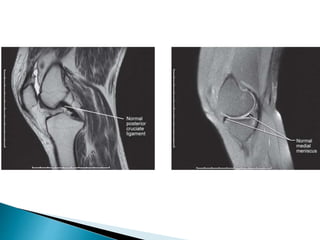

 Knee – ◦Meniscal tears ◦ Degenerative conditions of meniscus ◦ Ligament tears ◦ Patellar or quadriceps tendon tears ◦ Tendinitis ◦ Cysts ◦ Synovial pathology ◦ Occult fractures ◦ Popliteal mass ◦ Physeal injuries in children.

 Introduction - Magnetic resonance imaging

produces cross-sectional images of any body part

in any plane. It yields superb soft-tissue contrast,

allowing different soft tissues to be clearly

distinguished, e.g. ligaments, tendons, muscle and

hyaline cartilage.